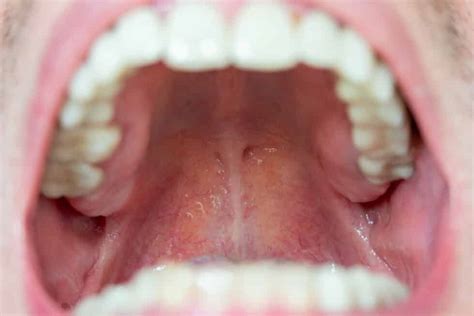

Características de un Paladar Sano

Iniciando con el aspecto de un paladar sano su apariencia se enfoca en la coloración uniforme y rosácea que emite el mismo. En principio, debería de presentar un color rosado muy saludable, sin cambios de tonalidad en ninguna parte. Una de las razones que te ayudarán a comprobar que tu paladar se encuentra totalmente sano es el color. Por esta razón, si tu paladar es de color rosa quiere decir que está sano, pero en caso de que presente un color blanco será hora de dirigirte al odontólogo.